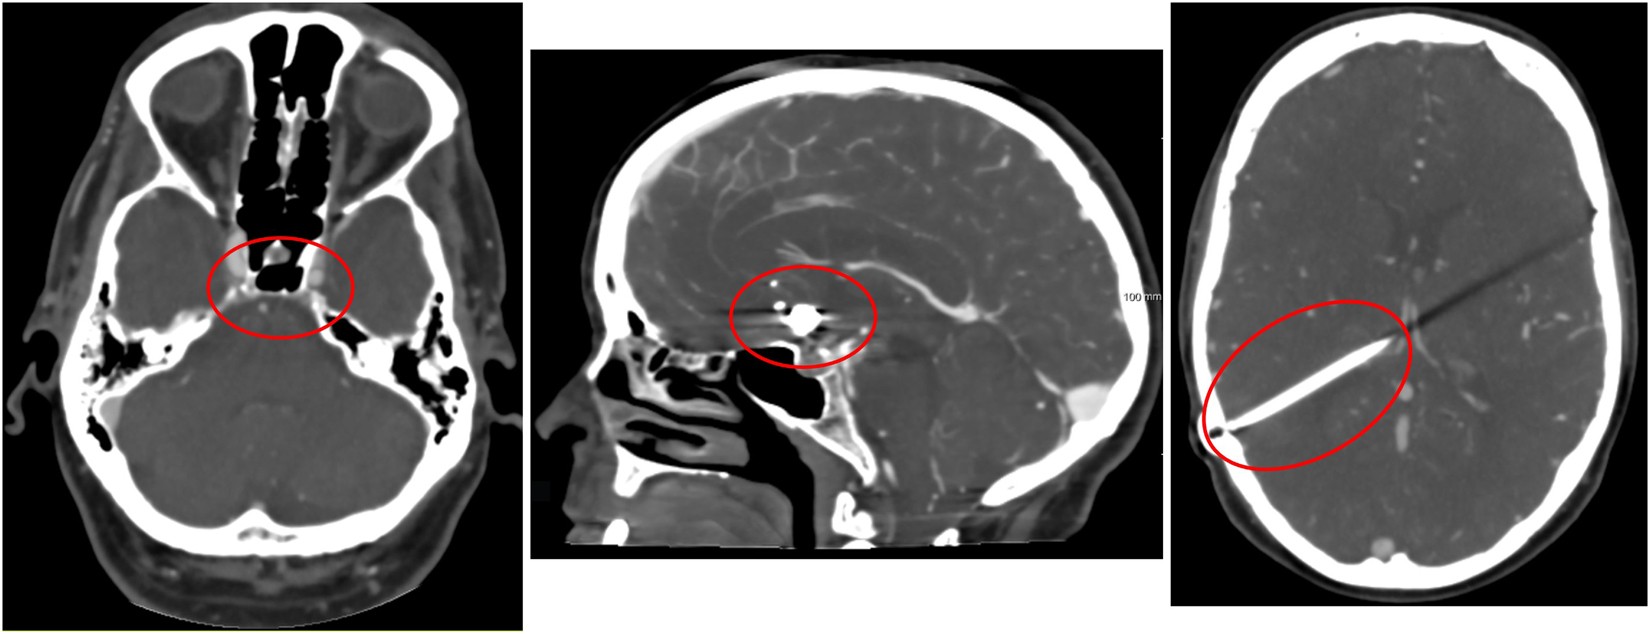

Figure 2

Examples of difficulties encountered in vessel segmentation. From left to right: Skull base region, arteries and veins surrounded by hyperdens bony structures in their course through the skull base, which renders difficulties in separating them from each other; patient with coils placed at the anterior communicating artery; patient with ventricular shunt causing a linear artifact in the left cerebral hemisphere.